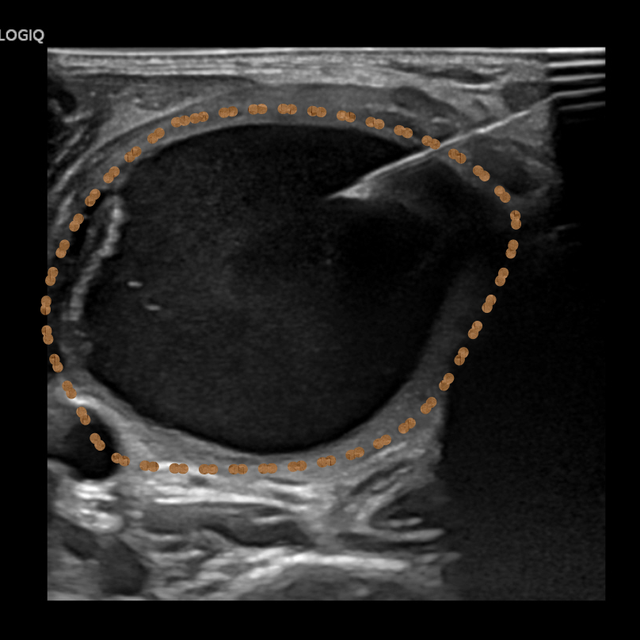

▲王晓明和张轶亮医师为患者行超声引导下肾囊肿穿刺抽液硬化治疗

超声介入团队联合妇科对患者进行全面综合评估后,认为超声引导下抽液硬化治疗是其最佳选择。待一系列术前常规检查后,在局部浸润麻醉下进行囊肿穿刺抽液硬化治疗。

治疗过程中,利用一步法置入一根“6F的猪尾巴管”,共抽出淡黄色液体220ml,部分送检行脱落细胞学检查。后用生理盐水对囊腔进行多次冲洗达清亮后抽出,注入40ml聚桂醇反复冲洗后留置,隔日抽出囊液50ml,此时囊液显示为酒红色,证明硬化效果较好,继续留置2日待负压球内基本无引流液后拔管。